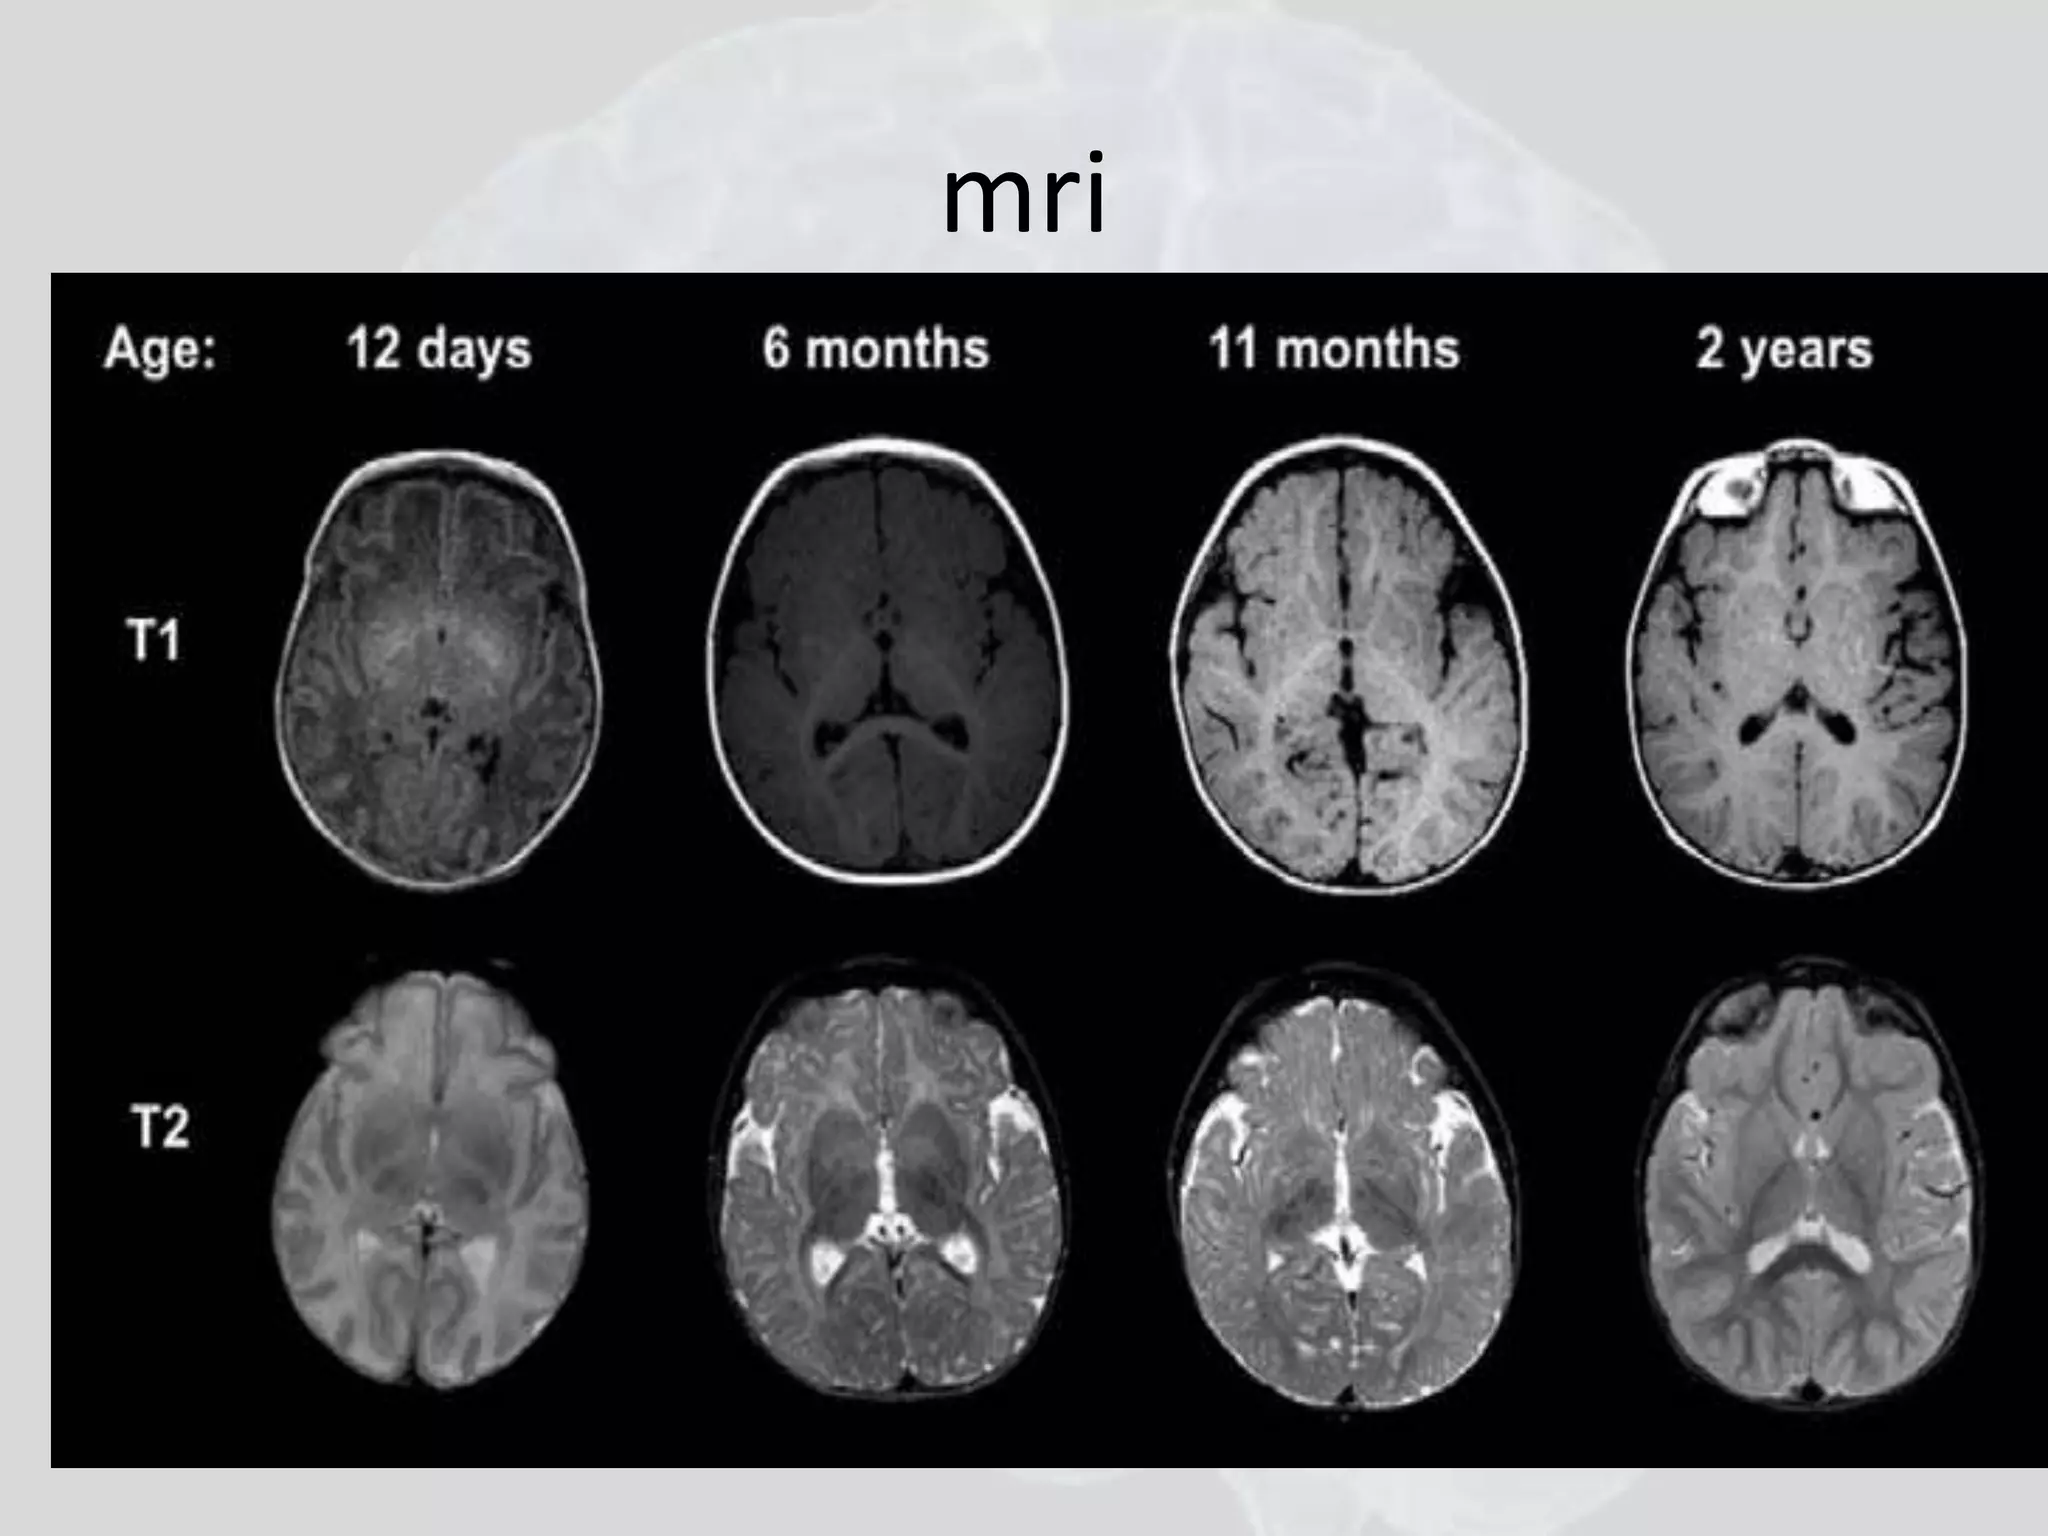

Myelination begins in the brainstem and extends

into the internal capsules and optic radiations by

6 months of life, forceps major and minor by 1

year, and into the gyral convolutions as in the

adult by a year and a half.

1 day 1 year 2 years

mri